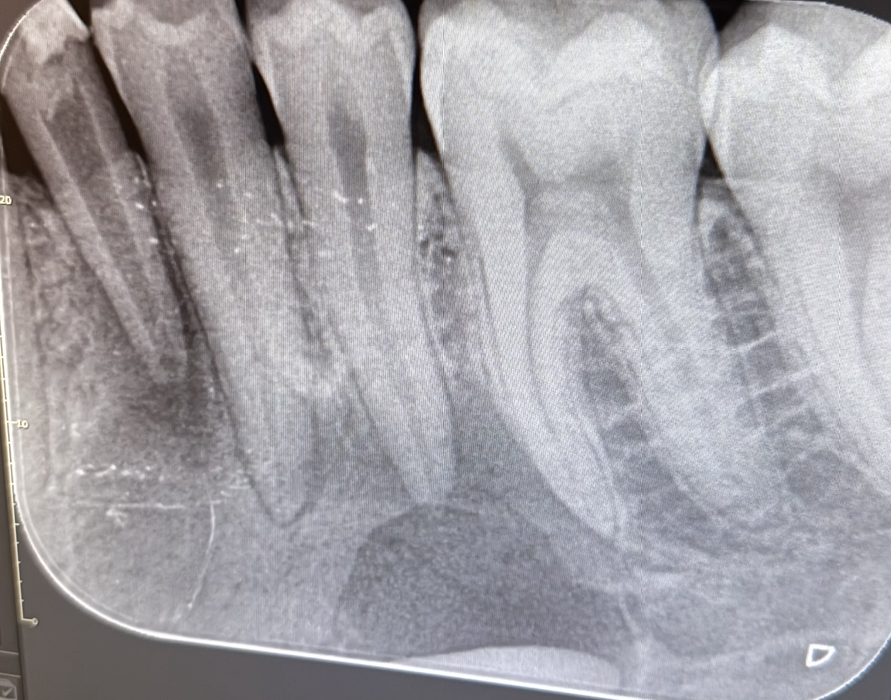

El paciente continúa bajo revisión, sin complicaciones hasta la fecha, habiéndose realizado un control radiográfico a los tres meses en el que se observa signos de remineralización (Figura 17).